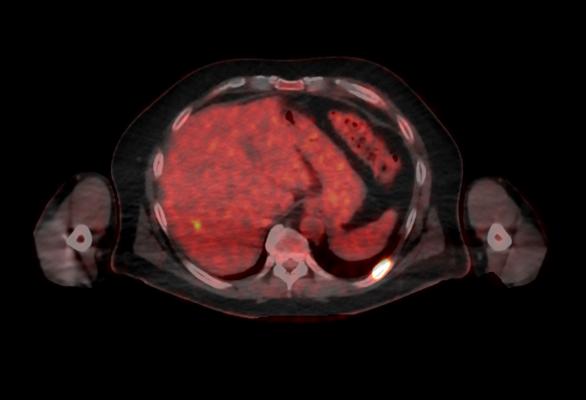

October 5, 2016 — GE Healthcare announced U.S. Food and Drug Administration (FDA) 510(k) clearance of its Discovery MI digital positron emission tomography (PET)/computed tomography (CT) system and shared a series of first clinical images. Built with technology allowing significantly better small lesion detectability, Discovery MI can help clinicians in their efforts to diagnose and stage disease earlier.

Discovery MI was created to help clinicians achieve their primary goal of diagnosing and staging disease earlier and to better guide their treatment strategies. It also enables more compelling research with more novel, faster decaying tracers. A key component in delivering these desired outcomes is Discovery MI’s LightBurst Digital Detector. This detector delivers up to two times improvement in volumetric resolution, enabling small lesion detectability, and has the highest NEMA sensitivity of any time-of-flight (TOF)/PET system in the industry, according to GE.

Discovery MI may also enhance clinicians’ diagnostic service offerings in oncology and expand PET’s impact in neurology, cardiology and beyond. These expanded capabilities are enabled by the ability to increase low-yield tracer capability with protocols that reduce dose by up to 50 percent, allowing clinicians to pursue research without impacting image quality.